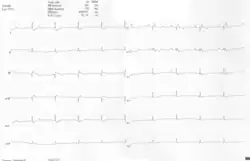

Other abnormalities that can be seen on the ECG include:

- signs of right atrial enlargement or tall and broad 'Himalayan' P waves

- first degree atrioventricular block manifesting as a prolonged PR-interval[7]

- low amplitude QRS complexes in the right precordial leads

- atypical right bundle branch block

- T wave inversion in V1-V4 and Q waves in V1-V4 and II, III and aVF.[8]